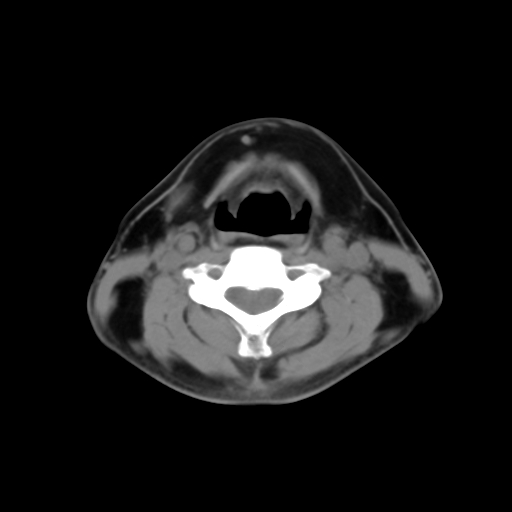

标题: CT24019:男,45岁,发现颈部肿物5个月。 [打印本页]

男,45岁,发现颈部肿物5个月,彩超示:双侧颈部及下颌部软组织增厚。

考虑双侧颈项部良性对称性脂肪增多症。